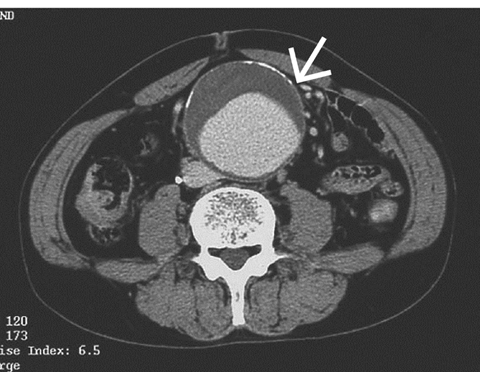

優先配送 【楽天市場】イラストレイテッド大動脈瘤手術 ブックスドリーム 参考書専門店 秀雄: 安達 医学一般